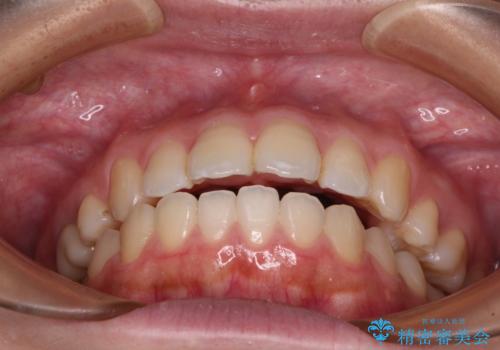

再矯正 開咬に後戻りした歯列をインビザラインで改善

インビザラインは前歯部の開咬に効果的であることが多く、ライトパッケージにもかかわらず、十分満足のいく仕上がりとなりました。